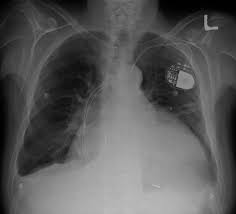

Chest X Ray Shows Cardiomegaly Cardiothoracic Ratio 52 Download Scientific Diagram